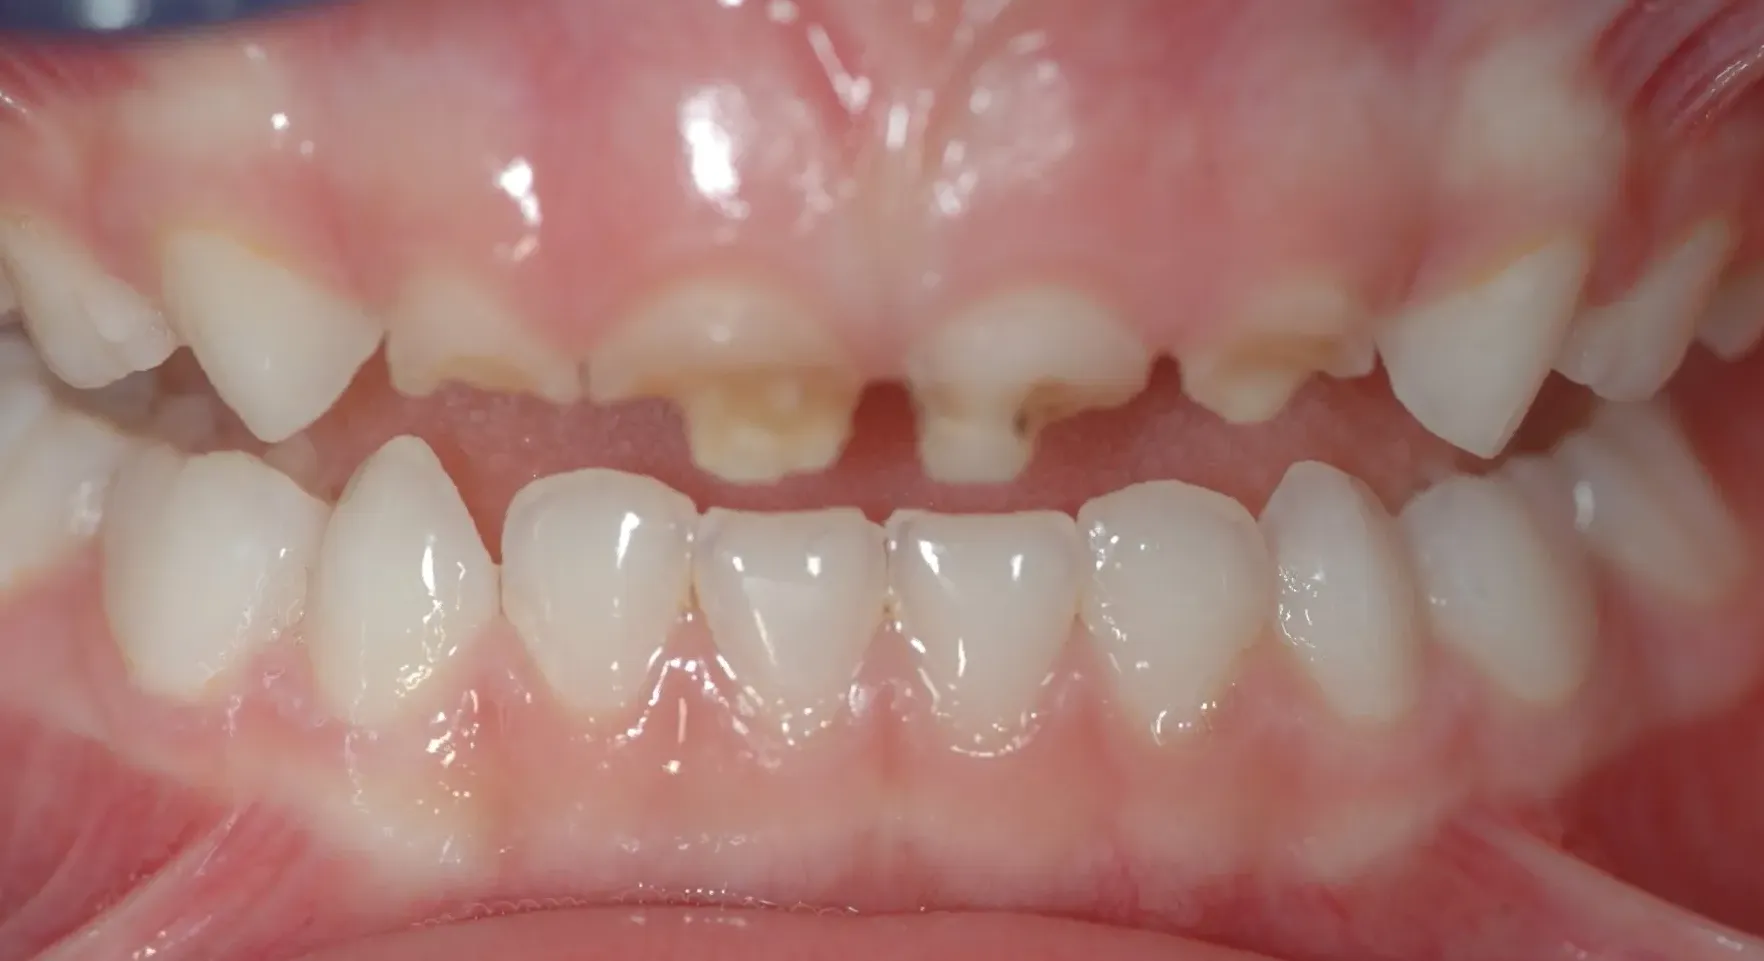

Frontzähne versorgen wir aus ästhetischen Gründen mit zahnfarbenen, direkt im Mund hergestellten Kunststoffkronen. Form und Funktion können auf diese Art optimal wiederhergestellt werden.

Stark kariös zerstörte Milchfrontzähne

Befund nach der Versorgung mit Kunststoffkronen